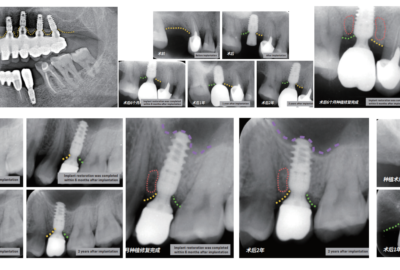

En este caso clínico se presenta el caso de un varón de 64 años con edentulismo total en la mandíbula superior durante más de 15 años. Tras explorar y evaluar el caso con CBCT y Rx, se propuso una solución de restauración fija con 8 implantes Esthetic Line de C-TECH después de un procedimiento de Regeneración Ósea Guiada.

Se utilizó hueso humano liofilizado de un banco de tejidos local para el injerto, mezclado con hueso autólogo y aloinjerto liofilizado. La cirugía de implante se realizó tras 16 semanas de curación, utilizando implantes C-Tech EL y técnicas de elevación del seno en senos altamente neumatizados.

Se emplearon pilares OMNI (una variante del Multi Unit) y se realizó una estructura de fibra de vidrio para la restauración, con coronas cerámicas Emax en los dientes anteriores y composite en los premolares y molares. La restauración final se atornilló en su posición definitiva.

Se puede observar una solución exitosa para la rehabilitación de la mandíbula superior con implantes C-Tech y un enfoque cuidadoso en la planificación y ejecución del tratamiento.